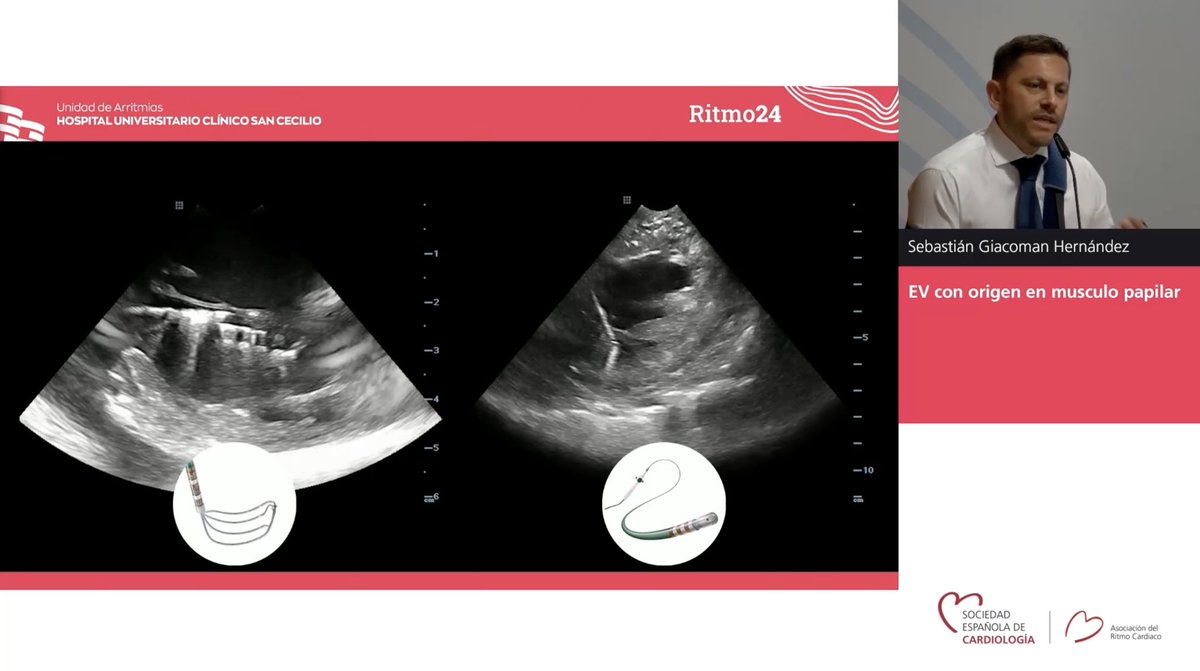

Continuamos con #Ritmo24, jueves 6, sala 10, Tips and tricks en ablación de EV con Fernando Arribas Sara Moreno, Angel Marínez, Jorge González-Panizo, Sebastian Giacoman Gerard Loughlin y luego sesión de nuevas herramientas en pacientes 👶🏻 y congénitos